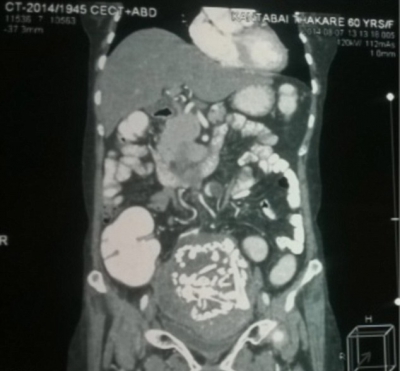

Ulterior, durerile au reapărut, iar femeia a trăit cu ele mulţi ani, fără să ştie foarte bine ce le cauzează. Recent, medicii care i-au făcut teste şi radiografii au încremenit.

O echipă se chirurgi de la spitalul din Nagpur a executat operaţie şi a extras din burta femeii scheletul fetusului vechi de 34 de ani.